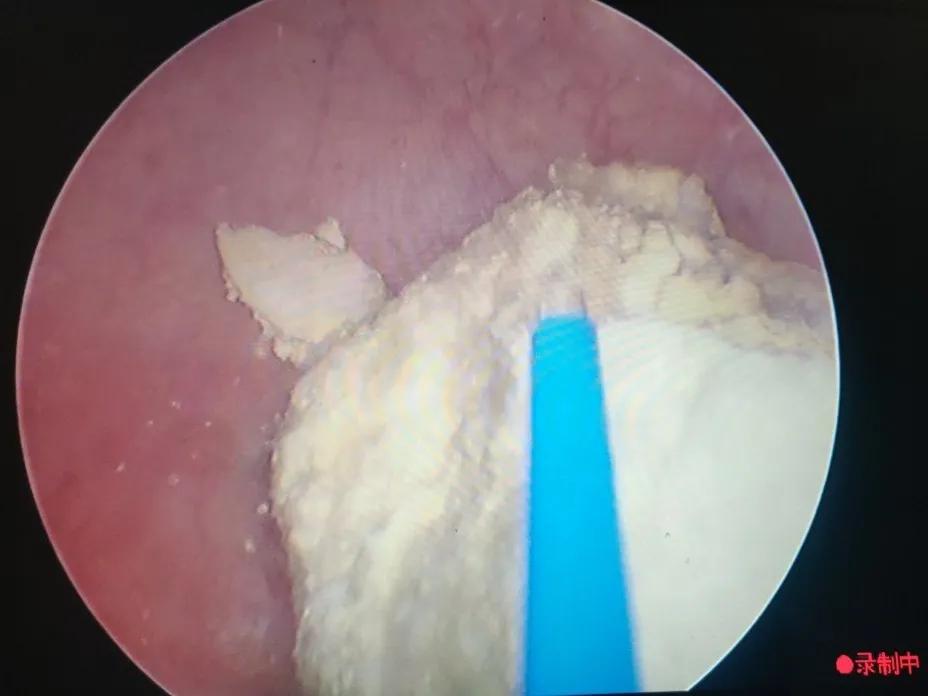

在手术室、麻醉科支持下手术开始,何晓北用钬激光一点点的将两枚结石击打成小碎块,随着结石的去除,节育环渐渐露出了真容,粉红色的两个端头丝毫不像能给患者带来剧烈腹痛的样子。何晓北用激光击打节育环的金属丝,靳永池带领的外一科团队紧盯着屏幕,做好了实施第二、三套方案的准备。随着几次亮光闪烁,节育环成功打断,接着从另一侧取出节育环剩余部分,去除碎石屑,手术顺利,成功结束。